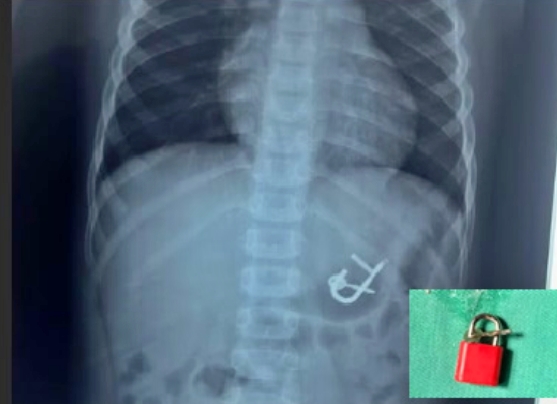

O diretor do hospital, Allain Carvalho, destacou que o cadeado ainda estava no

estômago da criança, o que facilitou sua remoção por endoscopia, evitando

procedimentos mais invasivos.